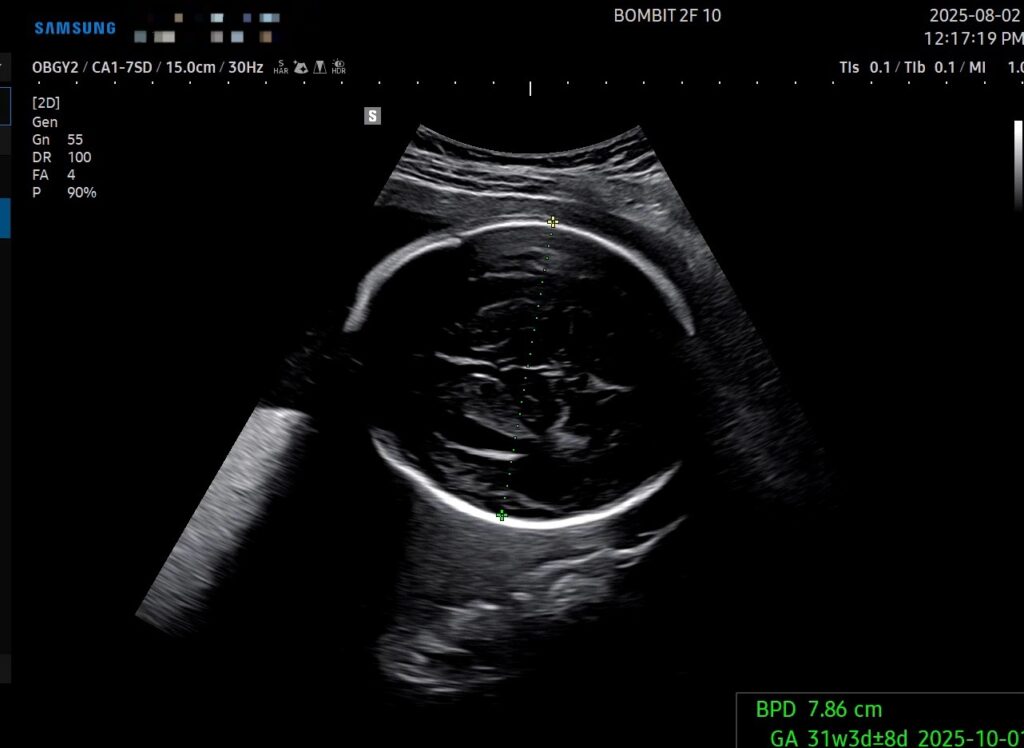

29주 6일차의 초음파인데, 몸무게, 배 둘레, 다리 길이 기준으로 주수는 약 32주로 나온다.

예상 몸무게는 1.958kg인데, 마미톡 주별정보의 30주차 적정 아기 무게는 1.4kg이라고 나온다. 아무리 초음파 측정이 오차범위가 있다지만 단비가 과도하게 큰 건 맞는 듯 하다 ㅜㅜ

- 두상이랑 다리길이는 이 친구 스타일이다. 즉 골격 자체는 원래 이 친구가 큰 아이라서 그런 것이다.

- 다만 배 둘레는 더 통통하냐 아니냐의 변화가 생길 수 있는데, 지금 내가 할 수 있는 건 혈당 관리 뿐이다.